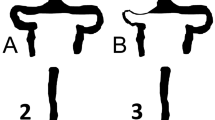

For each patient, the surface areas of right and left jugular foramina (JF) were measured using the pencil ROI method on axial MPR reconstructions (Fig. 1A, B) of the magnitude images from the PC-MRA sequence at the level of the skull base between the petrous temporal bone (laterally) and the jugular tubercle of the exocciput of the occipital bone (medially) according to Calandrelli et al. [21]. We considered smaller, larger, and mean values of JF areas for subsequent analysis. As the JF measurement method had been originally developed and validated for use on 3D-T1-weighted volumes [21], intra- and inter-rater reliability of JF measurements in the current experimental setup were preliminarily measured. To this end, on a subset of 74 studies, JF areas were measured twice 2 weeks apart by two neuroradiologists with at least 10 years of experience (CR and AC). Intra-class correlation coefficient (ICC) of the pooled right and left foramina measures was measured to assess intra-operator reliability. To measure intra-operator reproducibility, these 74 studies were also processed twice by one of the two neuroradiologists (CR). Jugular foramen areas were remeasured also on 29 MR exam including T1-weighted volumetric sequences (1-mm slice thickness) to validate the measure performed on the 3D PC-MRA sequences (1.6-mm thickness).

In particular, the area of the smaller jugular foramen was significantly smaller in patients versus controls (43.1 ± 14.6 vs. 52.7 ± 17.8; p < 0.001 at Mann–Whitney U) (Fig. 2A) whereas no significant differences were observed in larger jugular foramen areas (60.0 ± 19.7 vs. 61.4 ± 19.5; p < 0.478) (Fig. 2B). This resulted in a significantly smaller mean jugular foramen area in patients vs controls (51.6 ± 15.8 vs. 57.0 ± 18.3; p = 0.043) (Fig. 2C).

A The smaller JF area of patients with EH are significantly smaller than the smaller JF area of controls. B The larger JF area of patient do not statistically differ from the larger JF area of controls. C The mean of JF areas of patients with EH is significantly smaller than the mean of JF areas of controls

A Four-month-old boy evaluated for progressive macrocrania > 98° percentile and delayed milestones. CT scan shows external hydrocephalus, right positional plagiocephaly, and significant jugular foramen asymmetry (left > right). B At twelve months of age, MRI showed increased size of jugular foramen that remain asymmetric, confirm external hydrocephalus C with mild ventricular dilatation and right postural plagiocephaly (CVAI 10.75). D PC-MRV in coronal view confirms the different size of jugular foramen with consequent different caliber of jugular veins (left > right) and E, F 3D reconstruction of PC-MRV show a venous obstruction grading score (VOGS) of 4 due to bilateral flow gap at the level of jugular foramina